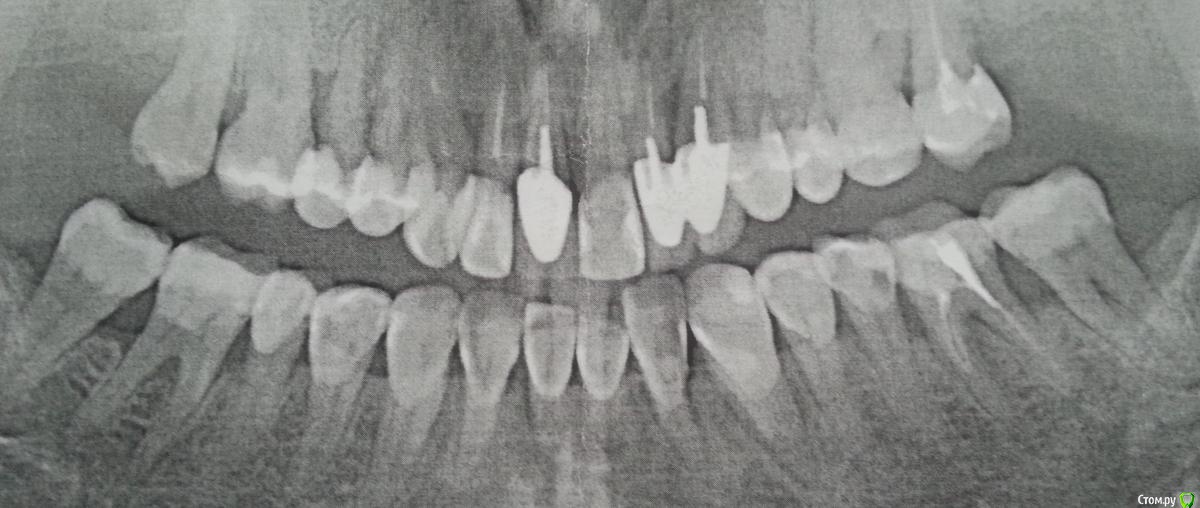

red_butler Опубликовано 29 марта, 2016 Поделиться Опубликовано 29 марта, 2016 На ваш взгляд там не больше 2мм до верхушки корня.Я этого не говорил, по Вашему снимку судить об этом не могу И ещё можно вопрос - действительно ли при горизонтальной резорбции невозможно нарастить кость при помощи мембран или ещё чего-нибудь?покажите ОПГ Ссылка на комментарий

Вадим Анат Опубликовано 29 марта, 2016 Автор Поделиться Опубликовано 29 марта, 2016 Я этого не говорил, по Вашему снимку судить об этом не могу покажите ОПГ Ссылка на комментарий

Вадим Анат Опубликовано 29 марта, 2016 Автор Поделиться Опубликовано 29 марта, 2016 Вот. Ссылка на комментарий

red_butler Опубликовано 29 марта, 2016 Поделиться Опубликовано 29 марта, 2016 Вот.по этому снимку все не так уж плохо, поддерживающая терапия продлит жизнь зубов. Но как раньше уже не будет. Что с прикусом?Да, кстати что у вас с полом, или шифруетесь? Я была Ссылка на комментарий